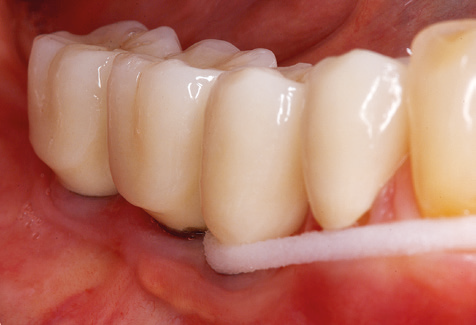

Following machine cleaning of the tooth and implant surfaces, the surfaces of the natural teeth are cleaned manually using standard hand instruments. When performing manual cleaning, particular attention must be given to maintaining the correct angle of application, appropriate sharpness, good support and working with the curette from apical to coronal. Either titanium or carbon curettes should be used for post-cleaning of the implant structures (Fig. 8). In addition to the use of ultrasonic devices, power jet devices can also be used in conservative dentistry. However, it must be taken into consideration that these procedures are not suitable for removing hard deposits and thus they cannot replace the use of hand instruments and ultrasonic instruments completely. In all cases, cleaning is followed by mechanical polishing of the accessible tooth and implant surfaces with polishing cups and polishing compounds (Fig. 9).

Standardised and regular risk-adapted care in the scope of SPT is the key to treatment success for the clinical long-term success in periodontically compromised patients. This is particularly true for patients fitted with implants following successfully completed periodontal treatment (Fig. 11a and b).

Fig. 4: Flexible probes with millimetre markings are recommended for the probing of dental implants (e.g. Colorvue Kit PCV11KIT6, Hu­Friedy). – Fig. 5a and b: A straight working tip (1P, W&H Dentalwerk Bürmoos GmbH) is a suitable instrument for use on all natural teeth. – Fig. 6: Curved working tips (3Pr/3Pl, W&H Dentalwerk Bürmoos GmbH) lend themselves to the processing of difficult-to-reach areas of the tooth and root surfaces (e.g. furcations). – Fig. 7: The tapered, hexagonal implant cleaning tip (1I, W&H Dentalwerk Bürmoos GmbH) permits atraumatic and efficient cleaning of the crown and abutment surfaces. – Fig. 8: Titanium and carbon curettes are suitable instruments for the manual cleaning of the implant surfaces.

Fig. 9: The accessible implant and tooth surfaces are polished with polishing cups and suitable polishing compounds. – Fig. 10: Repeat instruction in the use of appropriate aids for oral hygiene at home should also form part of SPT. – Fig. 11a and b: Clinical situation 12 years after insertion of the prosthetic restoration. During this period, only a veneering ceramic fracture on tooth 47 and the requirement for endodontic treatment of tooth 12 were observed. All restorations are still functioning as intended.